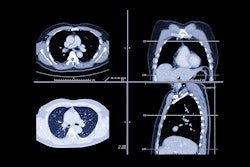

Kromek continues development of cadmium zinc telluride (CZT) detectors for photon counting CT and noted the launch of Spectrum Dynamics Medical's SPT/CT device Veriton-CT 300, which uses Kromek’s digital detectors, it said.